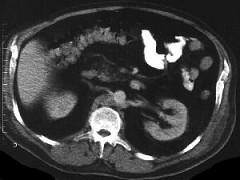

问题 中年男性,间断性腰背痛4个月,突发左下肢全肢水肿,小腿有张力性水泡,水肿累积会阴部,常规胸腹部CT扫描如图所示,你认为哪些征像及结论正确 ( )

选项 A、奇静脉变细 B、正常CT表现 C、下腔静脉变细 D、奇静脉增粗 E、下腔静脉缺如

答案 DE